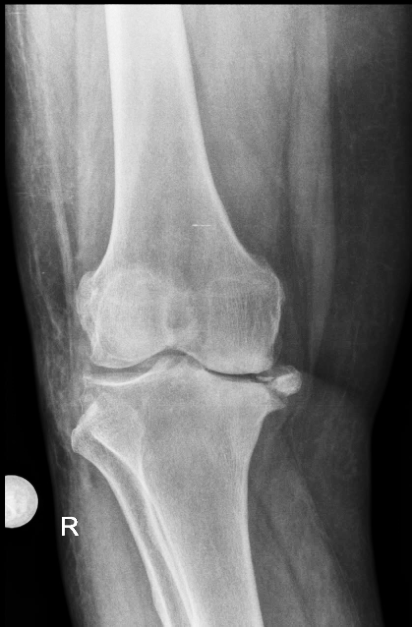

Клинический пример №2.

Посттравматический правосторонний гонартроз Rg III ст. Сросшийся перелом правой бедренной кости со смещением. Смешанная контрактура правого коленного сустава НФ 3 ст. Genu valgum.

После тотального цементного эндопротезирования коленного сустава эндопротезом De Puy Sigma.